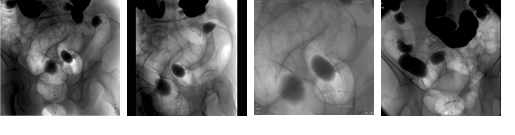

造影剤を注入して肝臓・胆嚢・膵臓・腎臓・腸などの腹部臓器の血管を染め出し、連続して血管の形の変化や異常を観察します。

腹部臓器や腹部血管の病気の診断。腹部臓器の手術の敵・不適、手術の方法や範囲の決定のために行われる検査です。